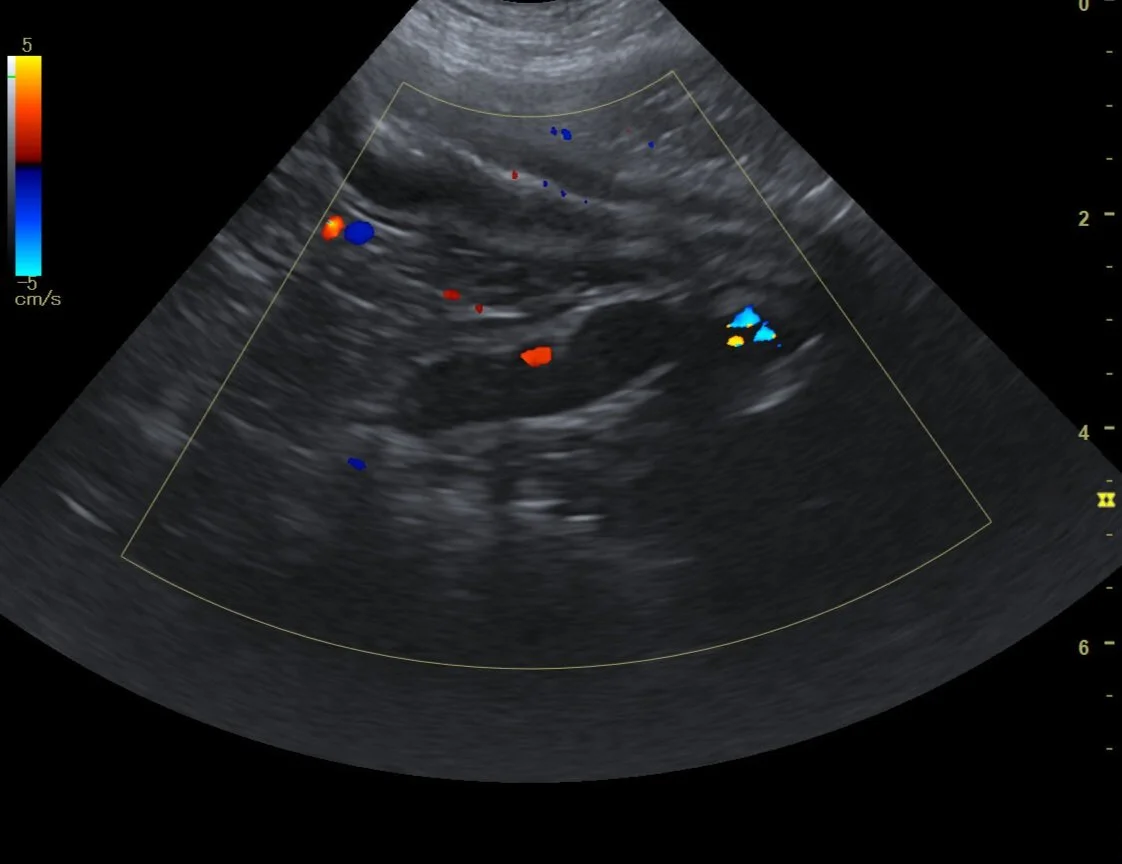

Our reports will include a detailed description of the organ system(s) being evaluated. All reports will include normal and abnormal findings from the exam. In some cases, we may include relevant ultrasound images from the exam so that you can see the pathologies and findings that are dictated in the report. All reports include findings, conclusions, and detailed recommendations.

Example Report Below ⬇️